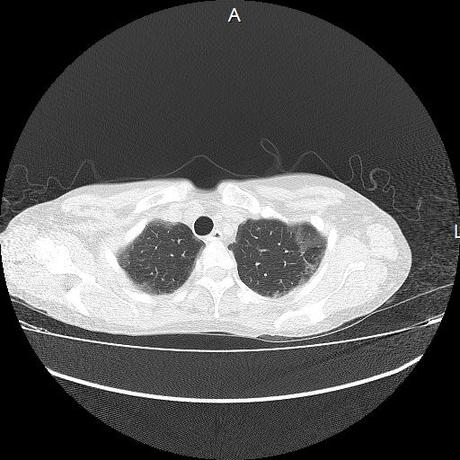

Se realiza volumen de tórax en fase simple, desde los opérculos torácicos hasta los hemidiafragmas, observándose:

El parénquima pulmonar con areas parcheadas difusas en vidrio despulido combinadas con otras areas hipodensas de baja atenuación debidas a atrapamiento aéreo y engrosamiento intersticial y zonas de fibrosis de predominio en lóbulos medios e inferiores de ambos pulmones.

- LOS HALLAZGOS PUEDEN ESTAR EN RELACIÓN A NEUMOPATIA INTERSTICIAL PROBABLE ETIOLOGIA HIPERSENSITIVA VS AUTOINMUNE/BACTERIANA/FUNGICA.